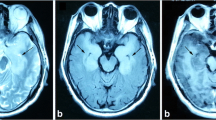

We detected one case of HSV-1 and another of VZV, which could not be confirmed by PCR due to insufficient clinical samples and were not previously detected with the FA/ME test. A recent study conducting diagnostic test accuracy meta-analysis (including sensitivity and subgroup analyses) reported suboptimal sensitivities for HSV-1, concluding that the FA/ME test is excellent for ruling in but limited for ruling out CNS infections [27]. Nonetheless, the patient improved with only 48 h of specific treatment and showed no typical radiological signs of herpetic encephalitis. We also detected CMV, which is one of the most clinically recognized viral pathogens in immunocompromised patients, in two cases not confirmed by specific PCR, possibly due to low viral load as suggested by the low rPM parameter from the CZ ID pipeline. For genomic detection of low virus concentrations, HCSS has proven more sensitive compared to untargeted shotgun sequencing [28].